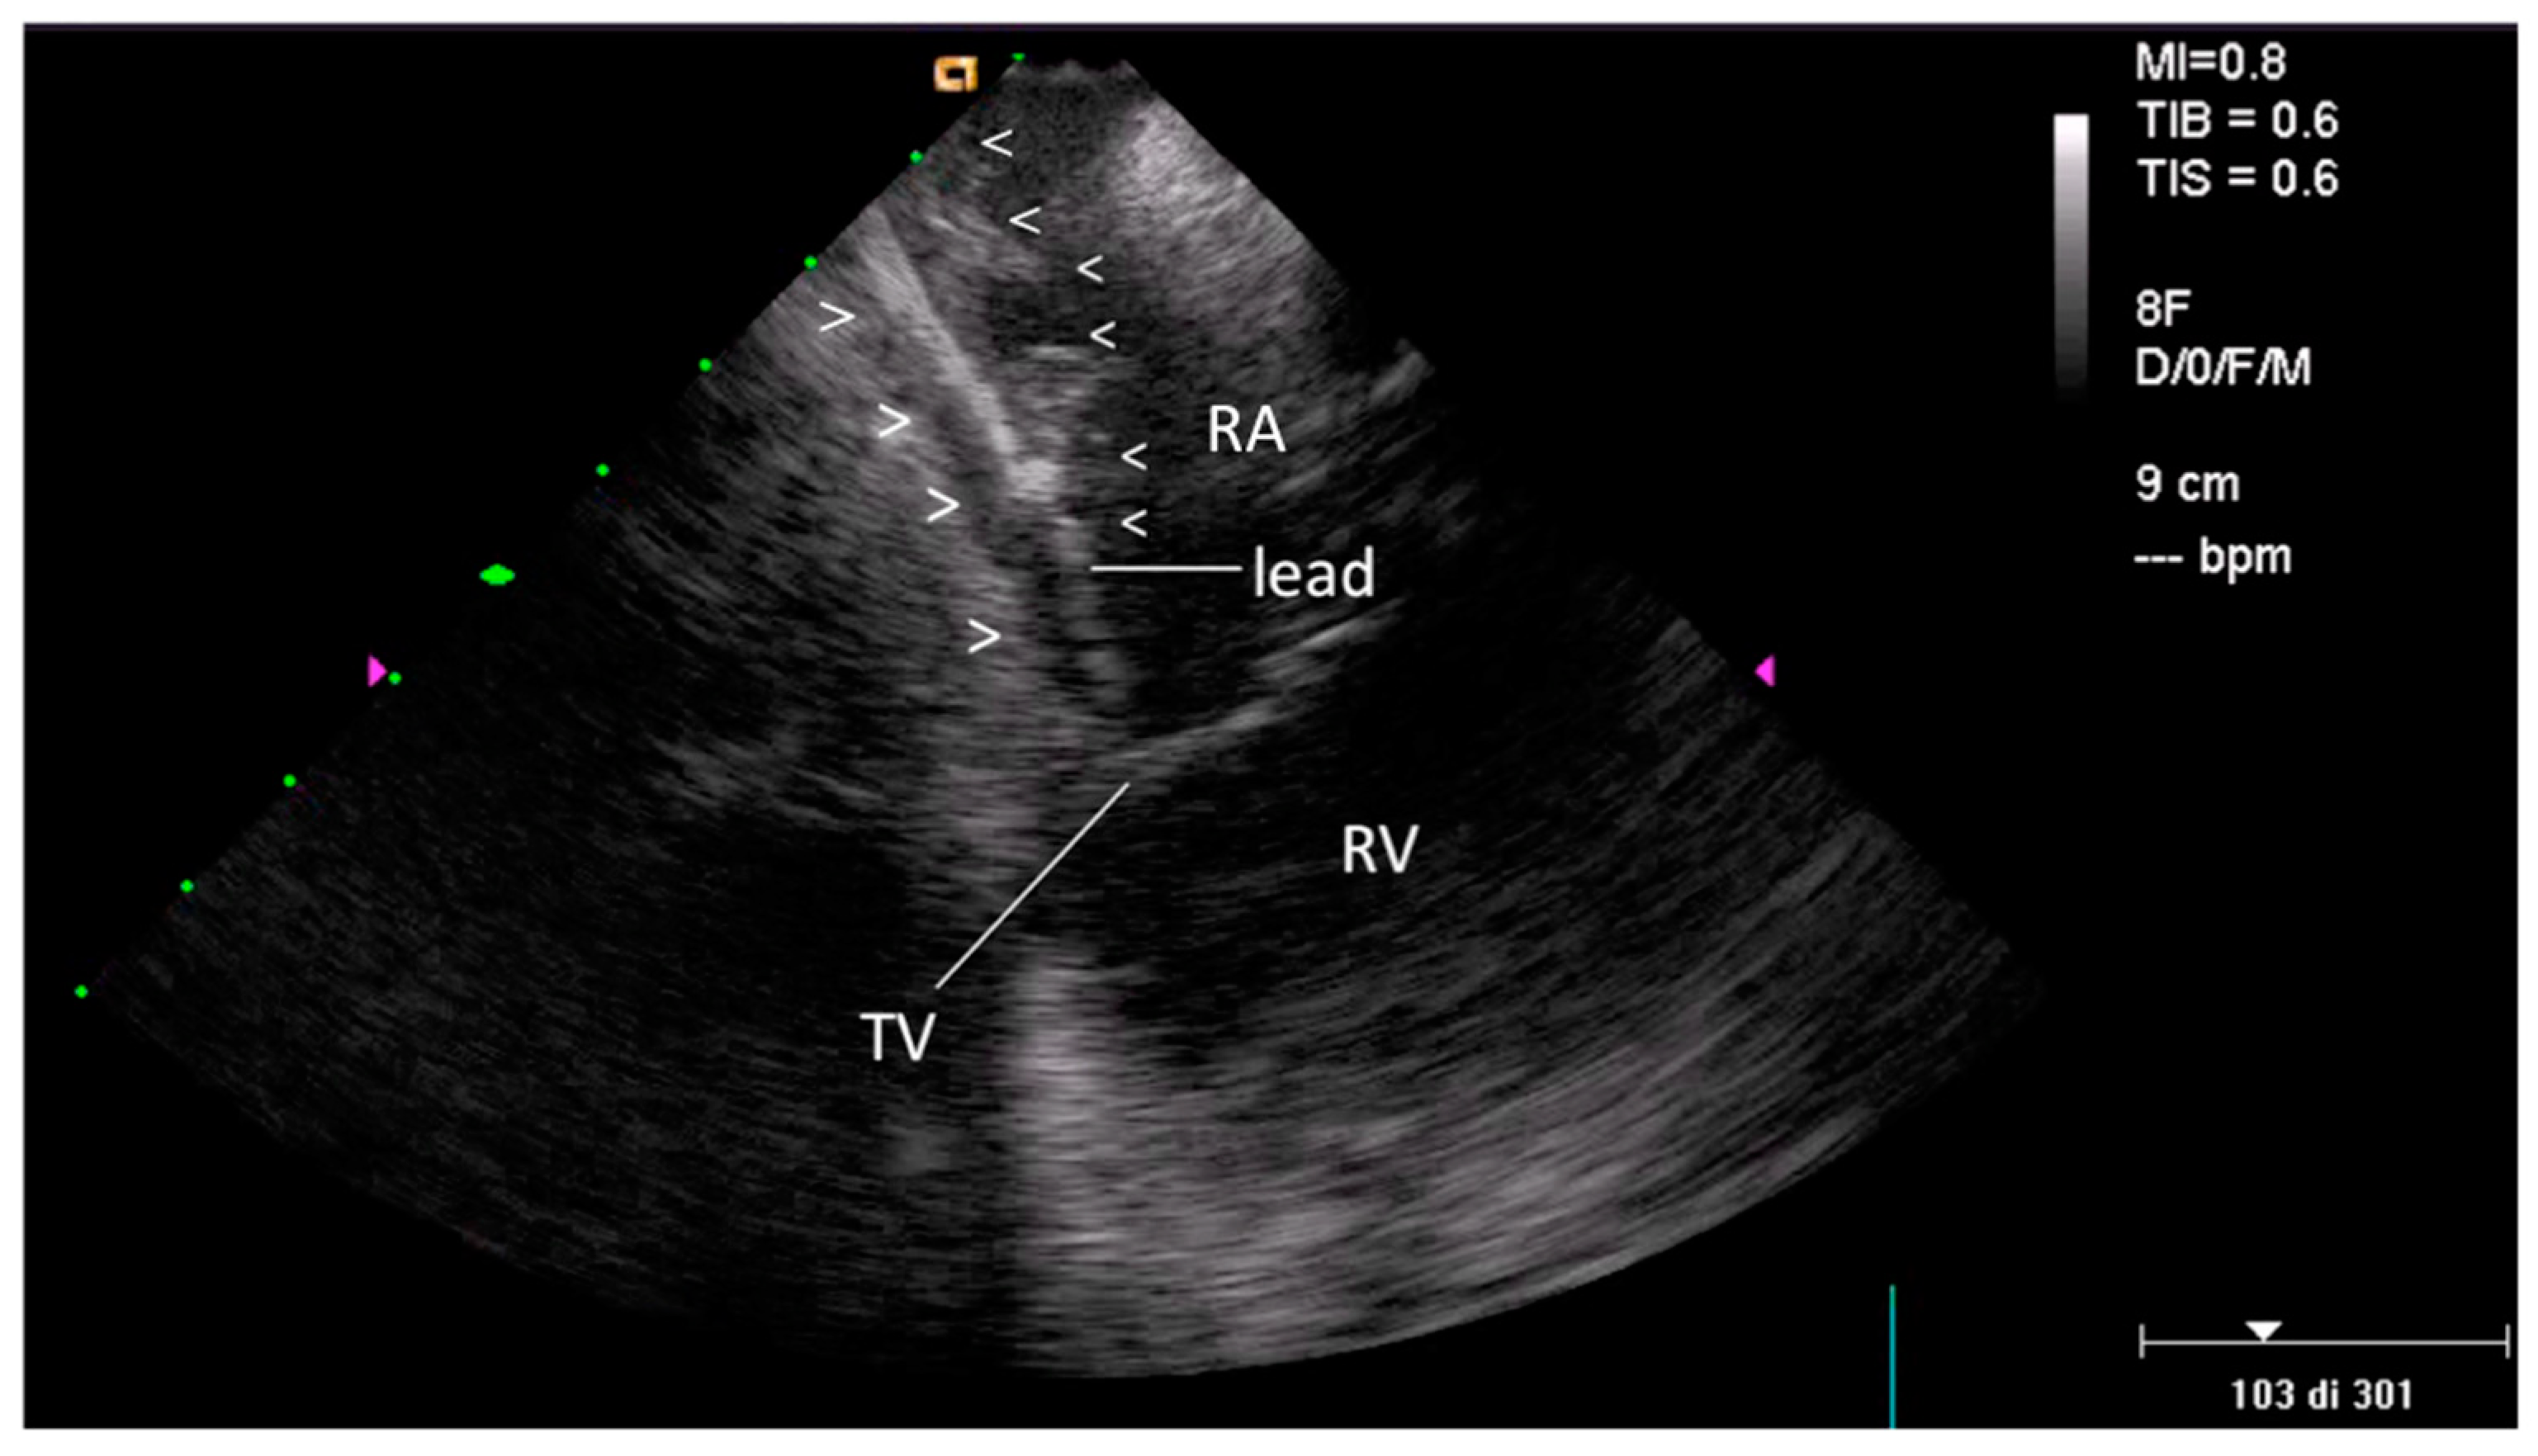

2.2.2. After the Extraction

3.2. Post-extraction ICE